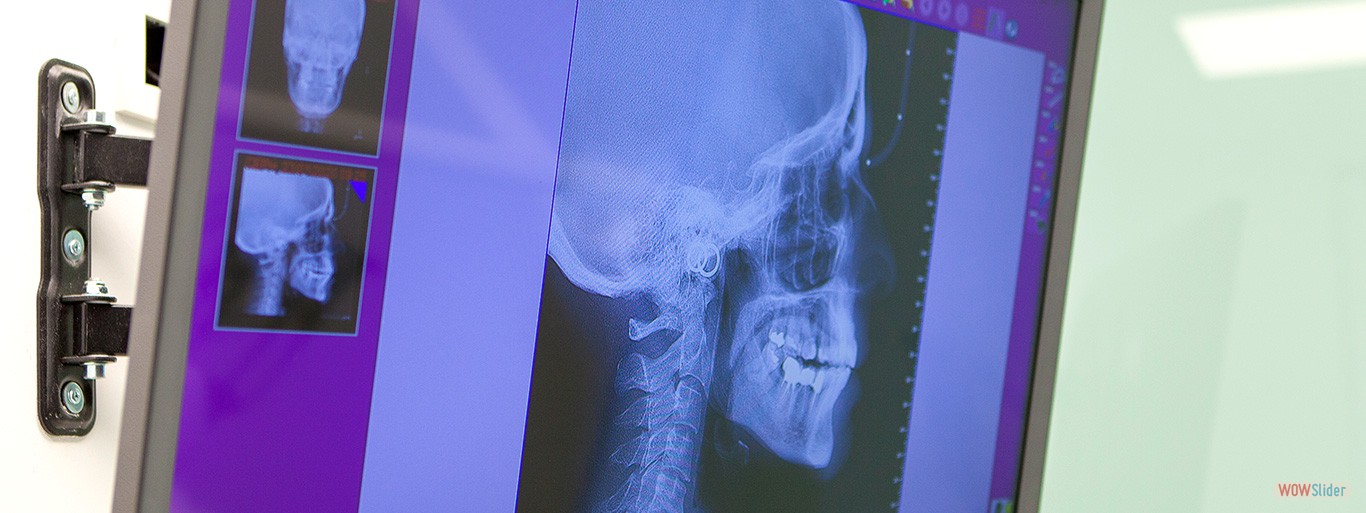

Nuestra clínica dental dispone de unas instalaciones modernas, dotadas con tecnología de vanguardia y especialistas expertos en cada tipo de tratamiento. Cuidamos todos los detalles para que nuestros pacientes dispongan de un espacio confortable con todos los medios necesarios para realizar los tratamientos dentales específicos.

En Clínica Dental Dr. Gustavo Compte disponemos de equipamientos de última generación para ofrecer a nuestros pacientes los mejores tratamientos para su salud bucodental. Entre ellos destaca el sistema de radiografía digital, escaner oral e intraoral y el sistema diagnóstico periodontal más rápido, preciso, y educacional de registro de sondaje periodontal.